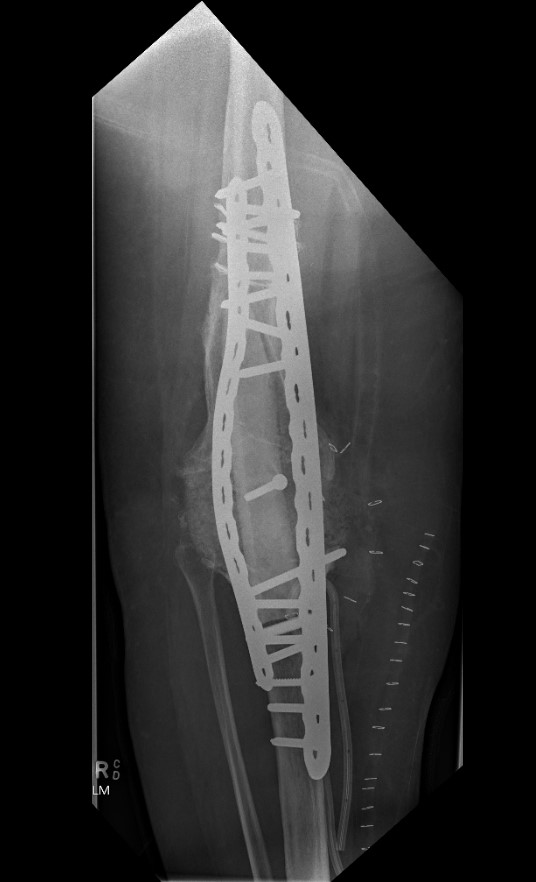

Dual plates